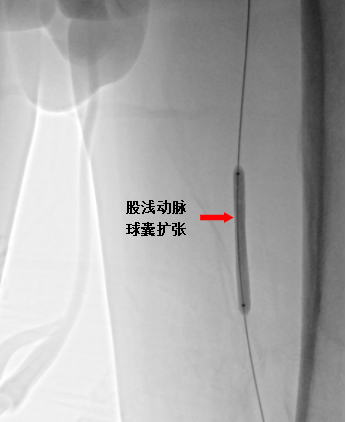

溶栓治疗后,后续又择期引入球囊导管,分别在左侧髂动脉、股浅动脉多处狭窄段进行球囊扩张,扩张后造影见血管扩张良好,血流通畅。